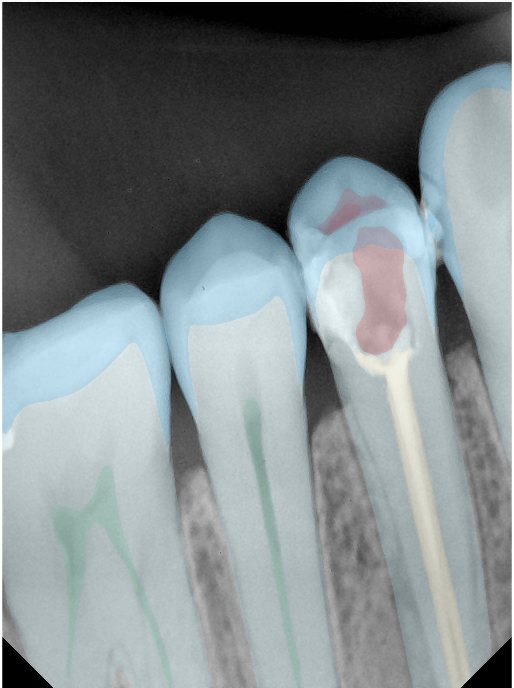

CR/DR 牙齿分割阶段记录

当前进展

- 完成了 CR/DR 牙齿相关分割训练

- 当前结果已经达到阶段预期,但仍有细节问题需要继续处理

相关测试

遇到的问题

- 训练过程中出现过 mask 下移问题

- 部分结果会出现 box 填充异常

- mask 边缘仍然有比较明显的锯齿感

参考

第二版算法问题测试

Updated: 2026-04-13(更新日期)

| 第一版 | 第二版 | 是否解决 | |

|---|---|---|---|

![]() | ![]() ![]() 边角识别有问题 龋齿识别不全 牙髓识别不全 | ![]() | 解决 |

![]() | ![]() 边角识别有问题 识别信息有误 自查(牙冠识别不全) | ![]() | 解决 |

![]() | ![]() ![]() 边角识别有误 大范围填充识别遗漏 | ![]() | 解决 |

![]() | ![]() 识别信息不全 | ![]() | 解决 |

![]() | ![]() ![]() 边角问题 牙胶识别不全 牙冠识别不全 | ![]() | 解决 |

![]() 换图片 | ![]() | ![]() 牙冠部分稍微白了一些就识别成小范围修补,部分判断异常 | 部分解决,修复类略敏感,牙冠部分稍微白了一些就识别成小范围修补,部分判断异常。 |

![]() | ![]() ![]() 牙冠识别不全 牙髓不全 根尖炎龋齿识别有误 | ![]() | 解决 |

![]() | ![]() | ![]() | 解决 |

![]() 换图片 | ![]() | ![]() | 解决 |

![]() | ![]() 牙冠识别有误 | ![]() | 解决 |

![]() 换图片 | ![]() ![]() 边角识别有误 | ![]() 修复类敏感 | 部分解决,图像过白,导致修复类判断异常。 |

![]() 换图片 | ![]() 牙冠识别不全 | ![]() 修复类敏感 | 部分解决,图像过白,导致修复类判断异常 |

结论:修复类出现了不鲁棒的情况,后续需要加入轮廓的扩充数据进行增强。